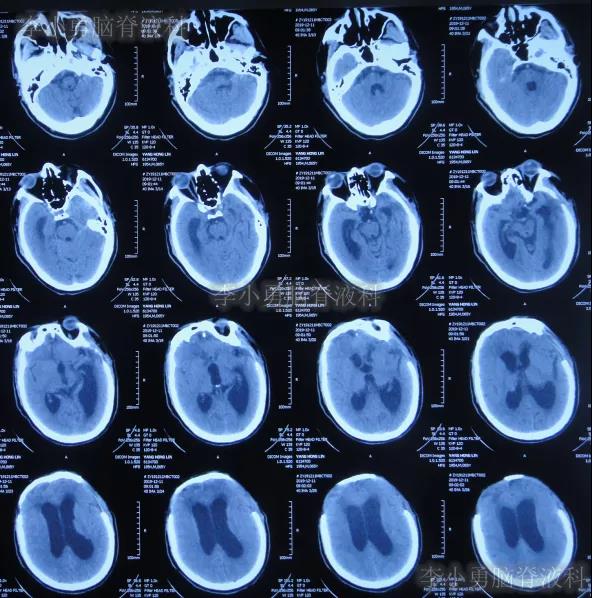

在第4家医院治疗26天,仍间断性发热、大小便失禁加重,住院期间曾2次查头颅CT(2020年2月27日(图-28)、2020年3月12日(图-29))示脑室仍扩张。

图-28:2020年2月27日头颅CT

图-29:2020年3月12日头颅CT

二、李小勇脑脊液科治疗过程和结果

2020年3月18日(颅脑外伤开颅术后149天即颅骨修补术后95天即第2次脑室腹腔分流术后62天,先后经4家医院治疗后仍意识模糊,大小便失禁,脑积水,间断发热近2月)转住入李小勇脑脊液科。入院时:意识模糊,大小便失禁,体重较前明显减轻,体温高38度左右;头部可见引流管走向;右侧肢体活动差些;鼻饲流食(图-30);入院时头颅CT示颅骨修补术后、脑室引流术后仍脑积水,有水肿(图-31)。

图-31:2020年3月18日头颅CT